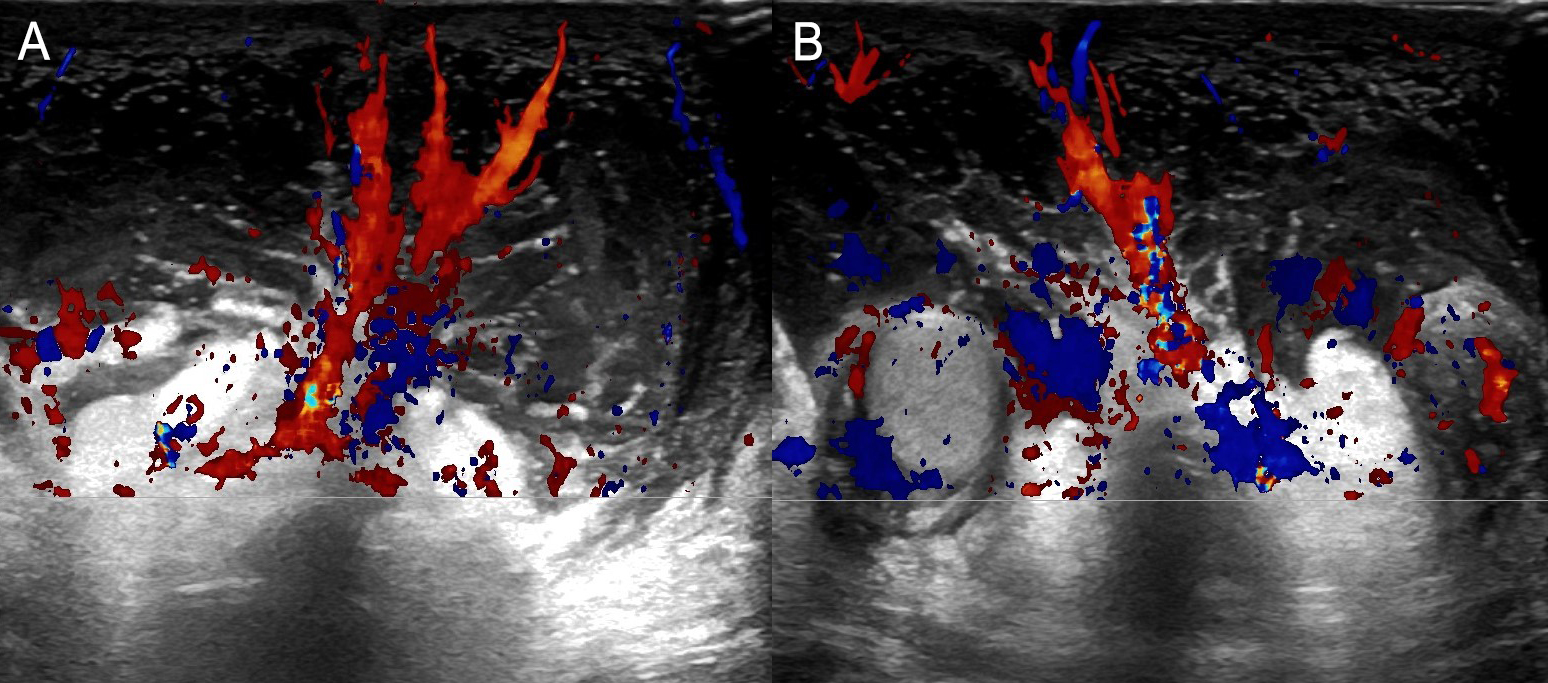

A 7-year-old boy, with no significant medical history, was admitted with complicated acute appendicitis and underwent an appendectomy. Two days after surgery, he developed painless, marked scrotal swelling. Physical examination revealed significant scrotal edema and erythema without tenderness. Ultrasound (US) showed diffuse hypoechoic thickening of the scrotal wall and pronounced subcutaneous edema, while the testes and epididymis appeared normal (Figure 1). Doppler imaging demonstrated marked bilateral hypervascularity in the scrotal wall, including the "fountain sign" (Figure 2), with normal intratesticular blood flow (Figure 3). These findings were consistent with acute idiopathic scrotal edema (AISE). The patient was managed conservatively with anti-inflammatory and antihistamine medication. The edema entirely resolved after four days, and a follow-up US confirmed the resolution of hypervascularity and edema.

Figure 2: Transverse Color Doppler scans (A and B) showing the "fountain sign" (increased scrotal wall blood flow, resembling a colored fountain).

From a radiological perspective, the diagnosis of AISE is often established using US, which is the modality of choice due to its non-invasive nature and high sensitivity for scrotal pathology.2 US findings typically include diffuse thickening of the scrotal wall and marked subcutaneous edema, with unremarkable testes and epididymis.1,2 Doppler imaging can further confirm the absence of testicular torsion by demonstrating normal intratesticular blood flow.3 A distinctive feature observed on Doppler imaging in AISE is the "fountain sign", characterized by hypervascularity in the scrotal skin and dartos fascia, due to increased flow in the anterior and posterior scrotal arteries.3 This sign is considered a hallmark of AISE. It helps to differentiate it from other causes of acute scrotal swelling, such as epididymitis, orchitis, torsion of the appendix testis or testicular torsion, which usually present with more severe clinical symptoms and abnormal testicular findings on imaging.3